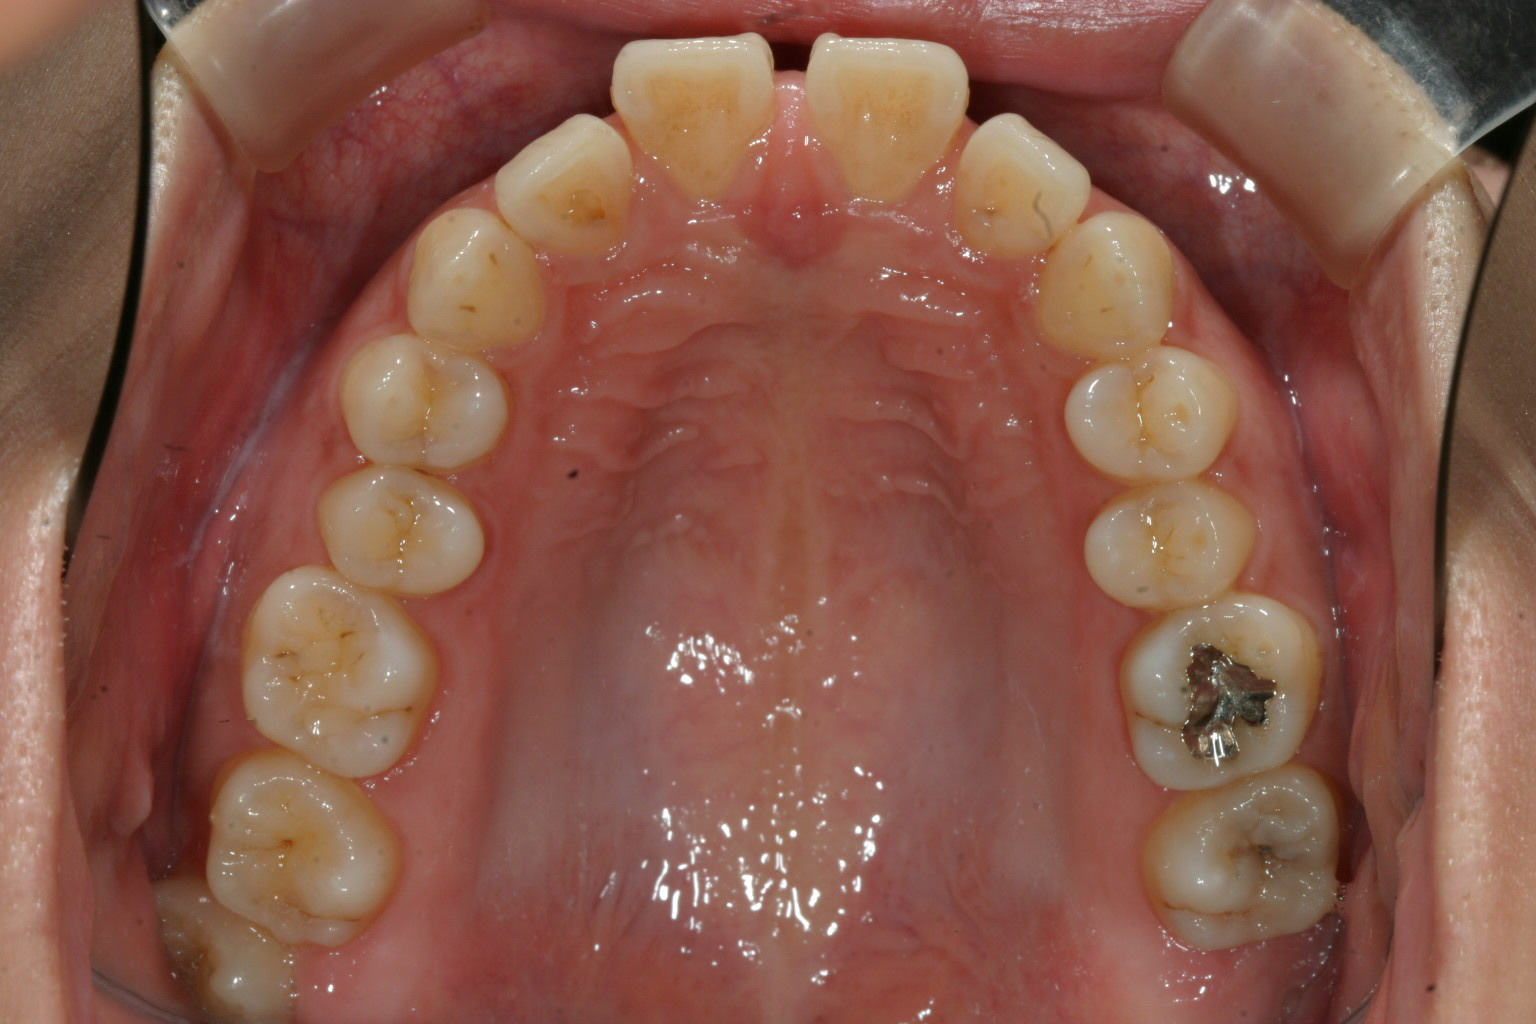

ここまで出てると本人的に気になりますね~ 真ん中もすきっぱですから。

下顎は綺麗な歯並びですね~

咬み合わせが深い為に前歯の歯茎を咬みこんでいる為前歯が前に出て隙間があいているという状態です。